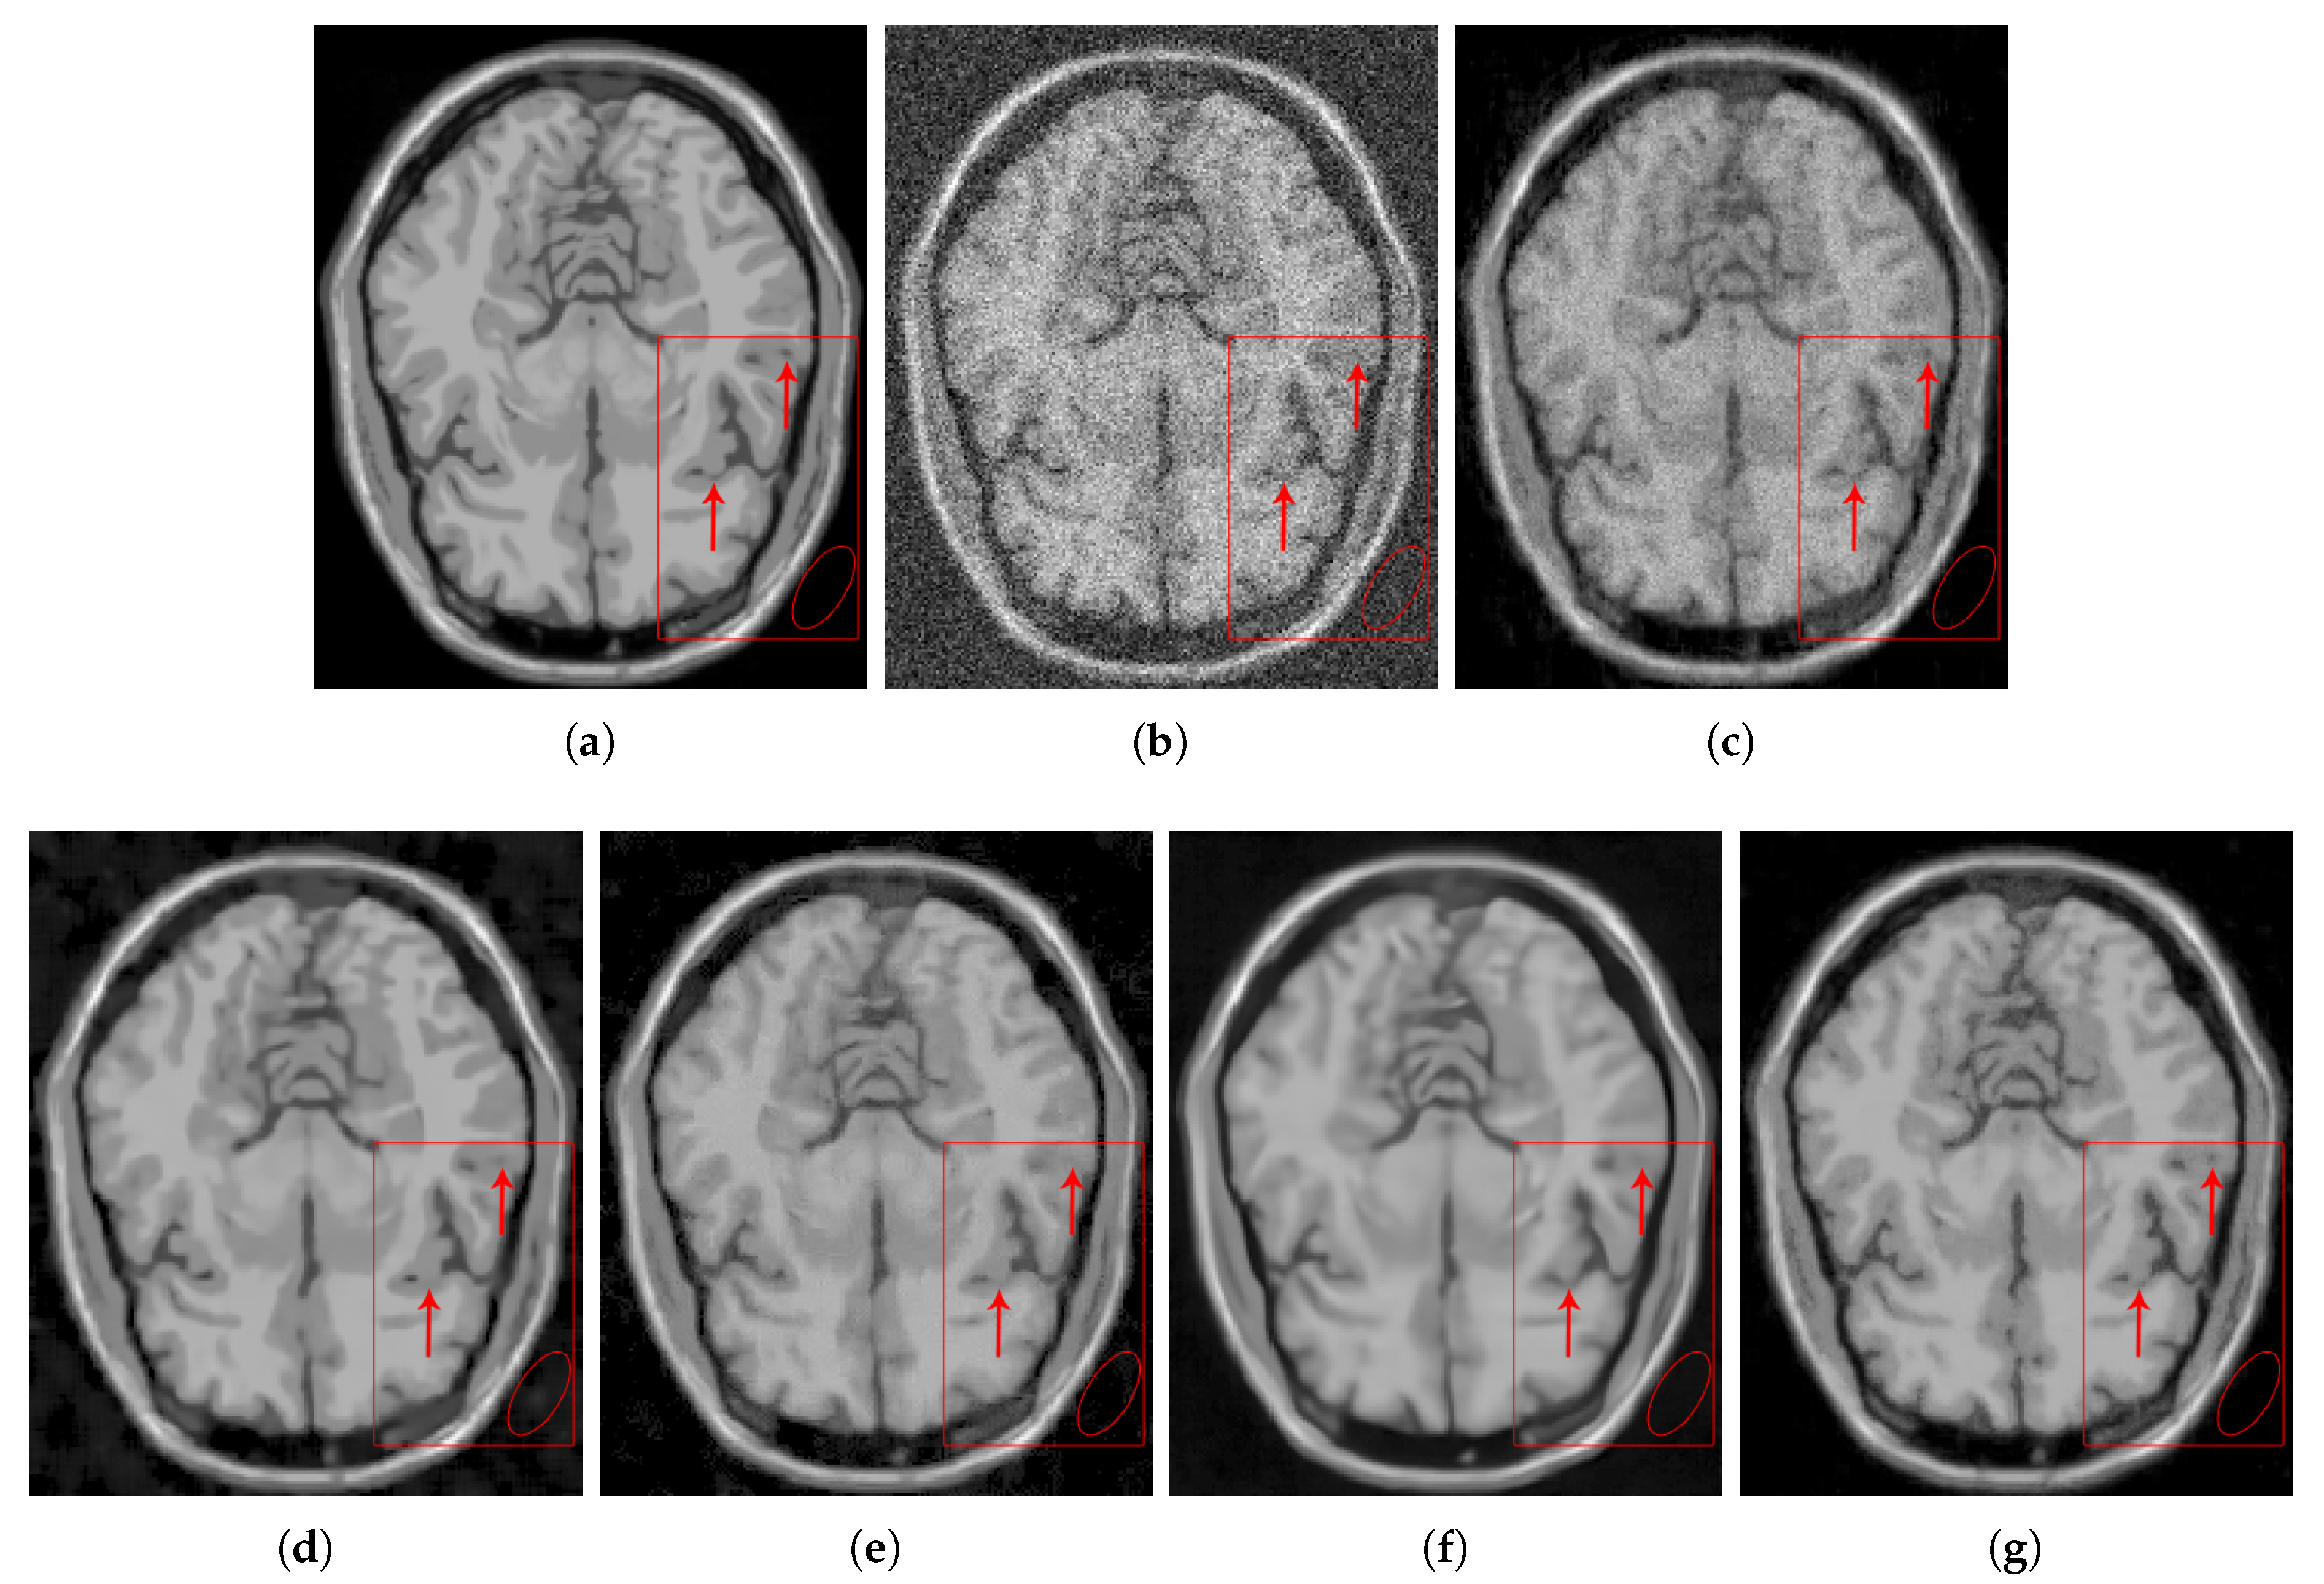

4.2.2. Real Data